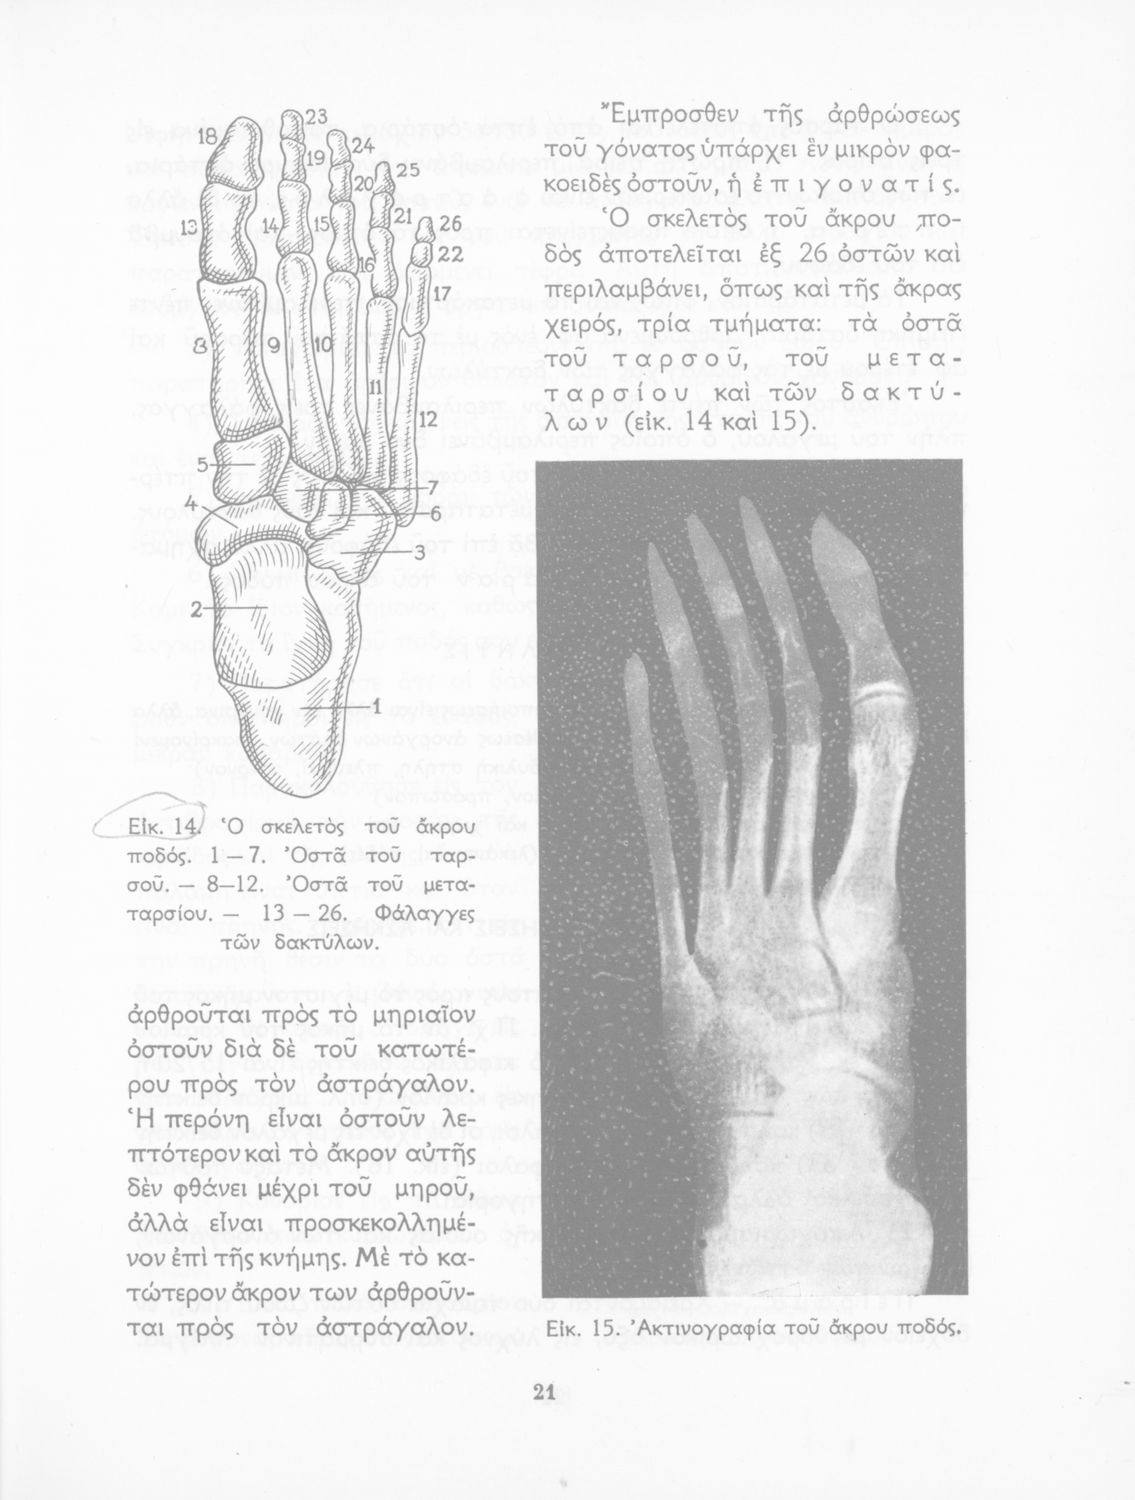

Σελίδα #021